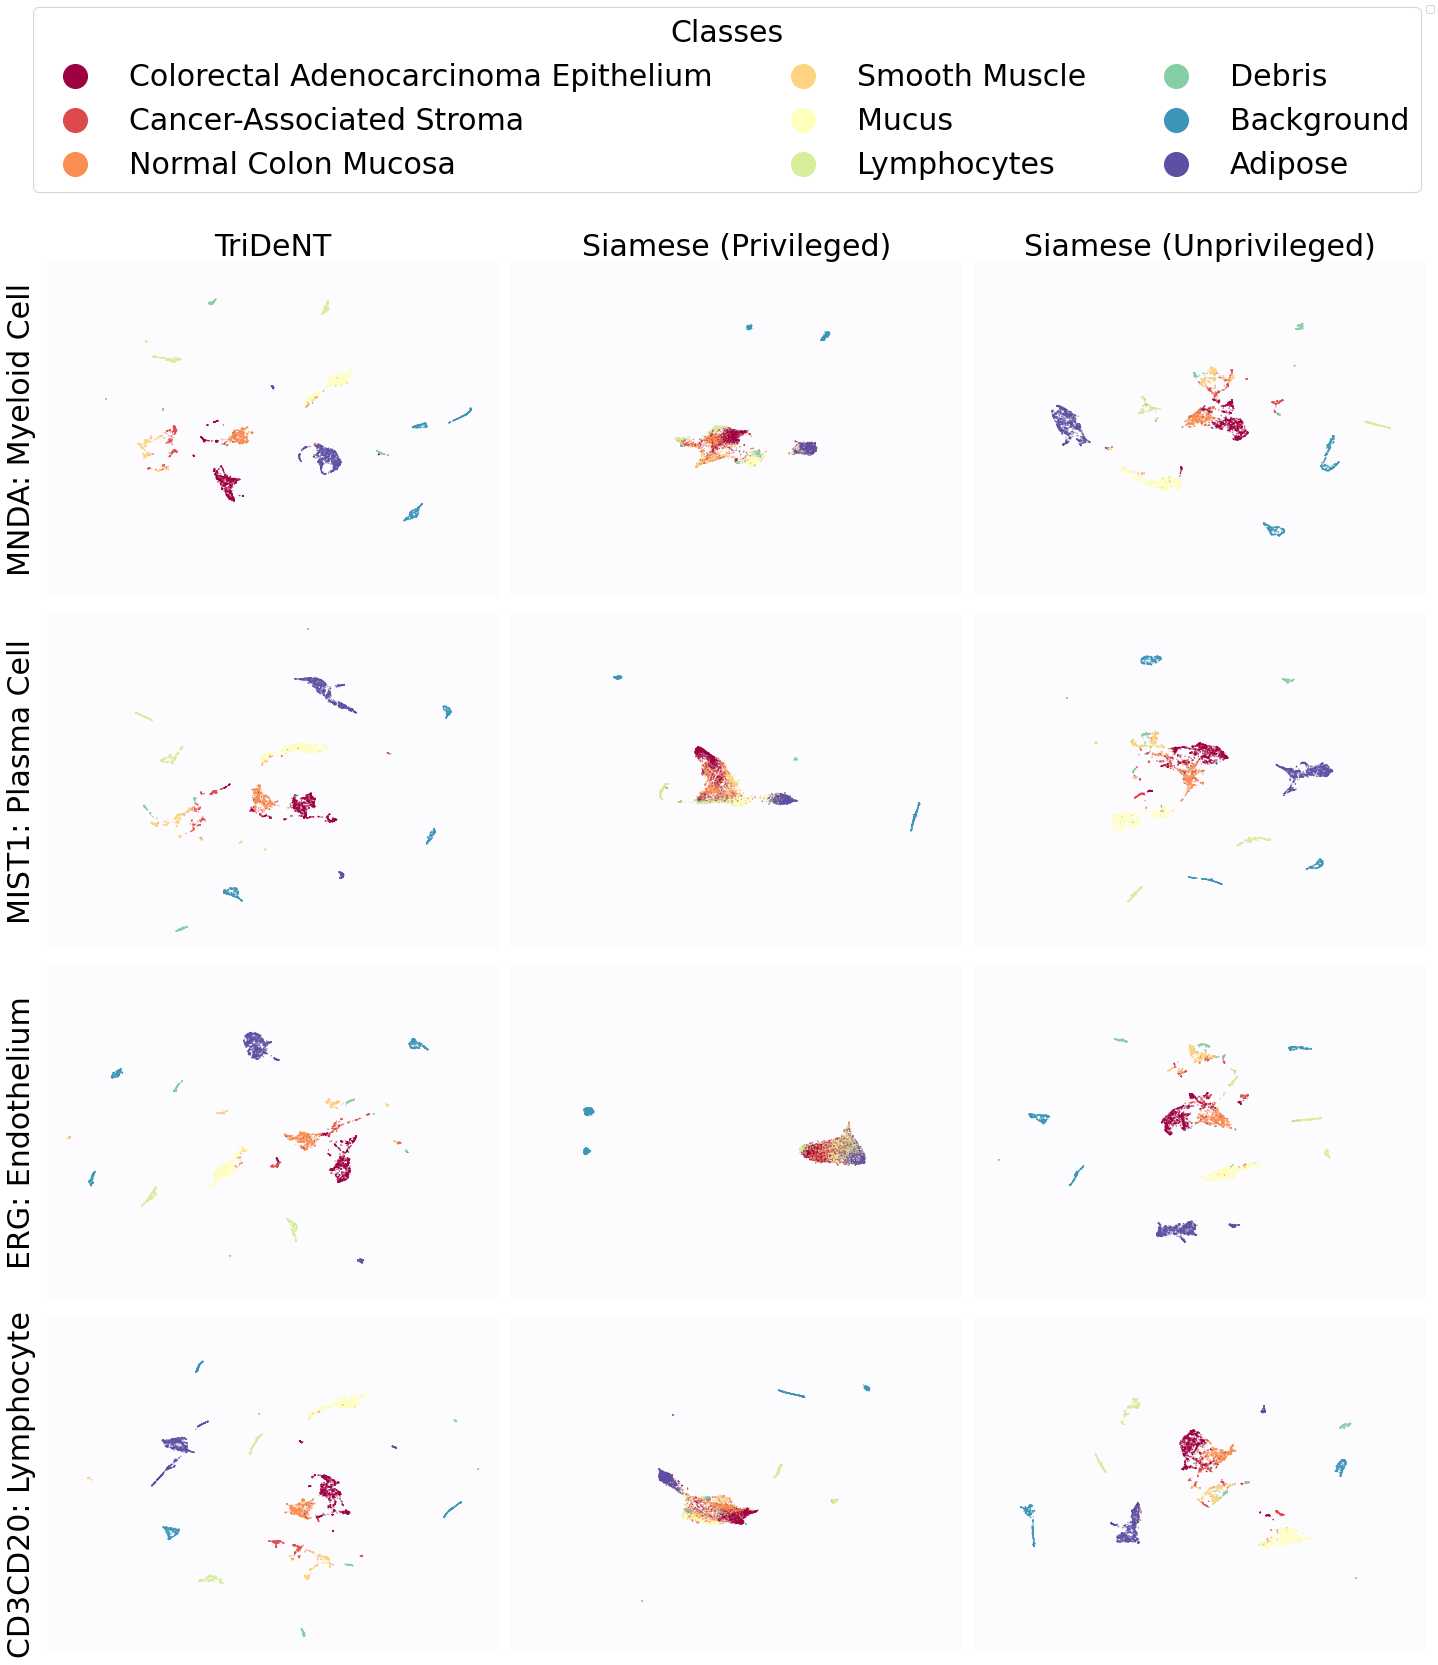

To further analyse the learned representations, we produce UMAP projections of the latent space labelled with the tissue types for the NCT tissue type classification task, as shown for CD3CD20 and SMA in Figure 4(a), and for all SegPath stains in Figures S8 and S9. These figures make the reasons for the varying performance of the privileged Siamese model more apparent. For stains with better performing privileged Siamese models, such as SMA, the UMAPs are very similar between Siamese methods and TriDeNT, with well-differentiated tissue type clusters. In those with worse performance, such as ERG, the tissue types are poorly differentiated, often with only adipose and background forming distinct clusters from the other classes. On closer inspection, it is notable in these projections that TriDeNT ♆ produces more well-defined and separated clusters in general than Siamese networks. This is further evidenced in Figure S7, where TriDeNT ♆ is shown to identify clusters with overexpression of a given gene significantly more effectively than an unprivileged Siamese model.